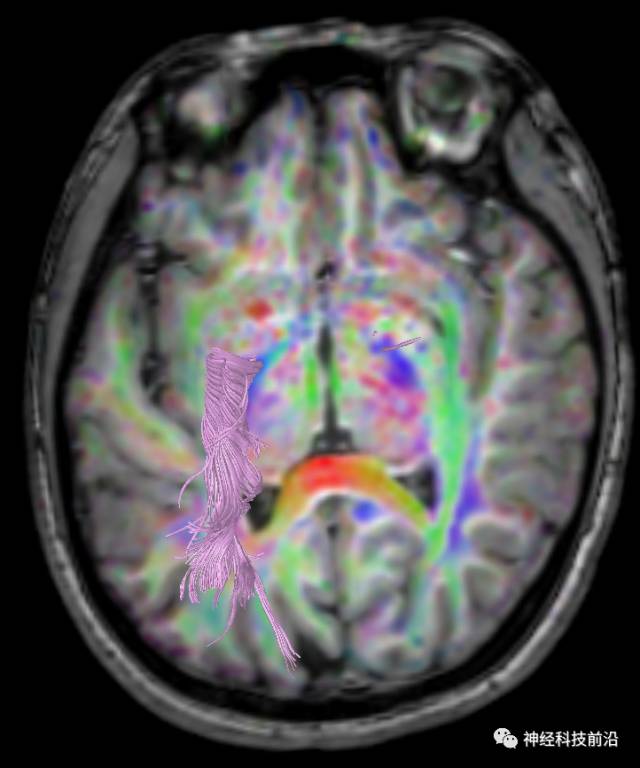

下面为皮质脑桥束的走形方位

皮质脑桥束与脑干高信号(黄色)纤维束

皮质脊髓束与皮质脑桥束的关系毗邻